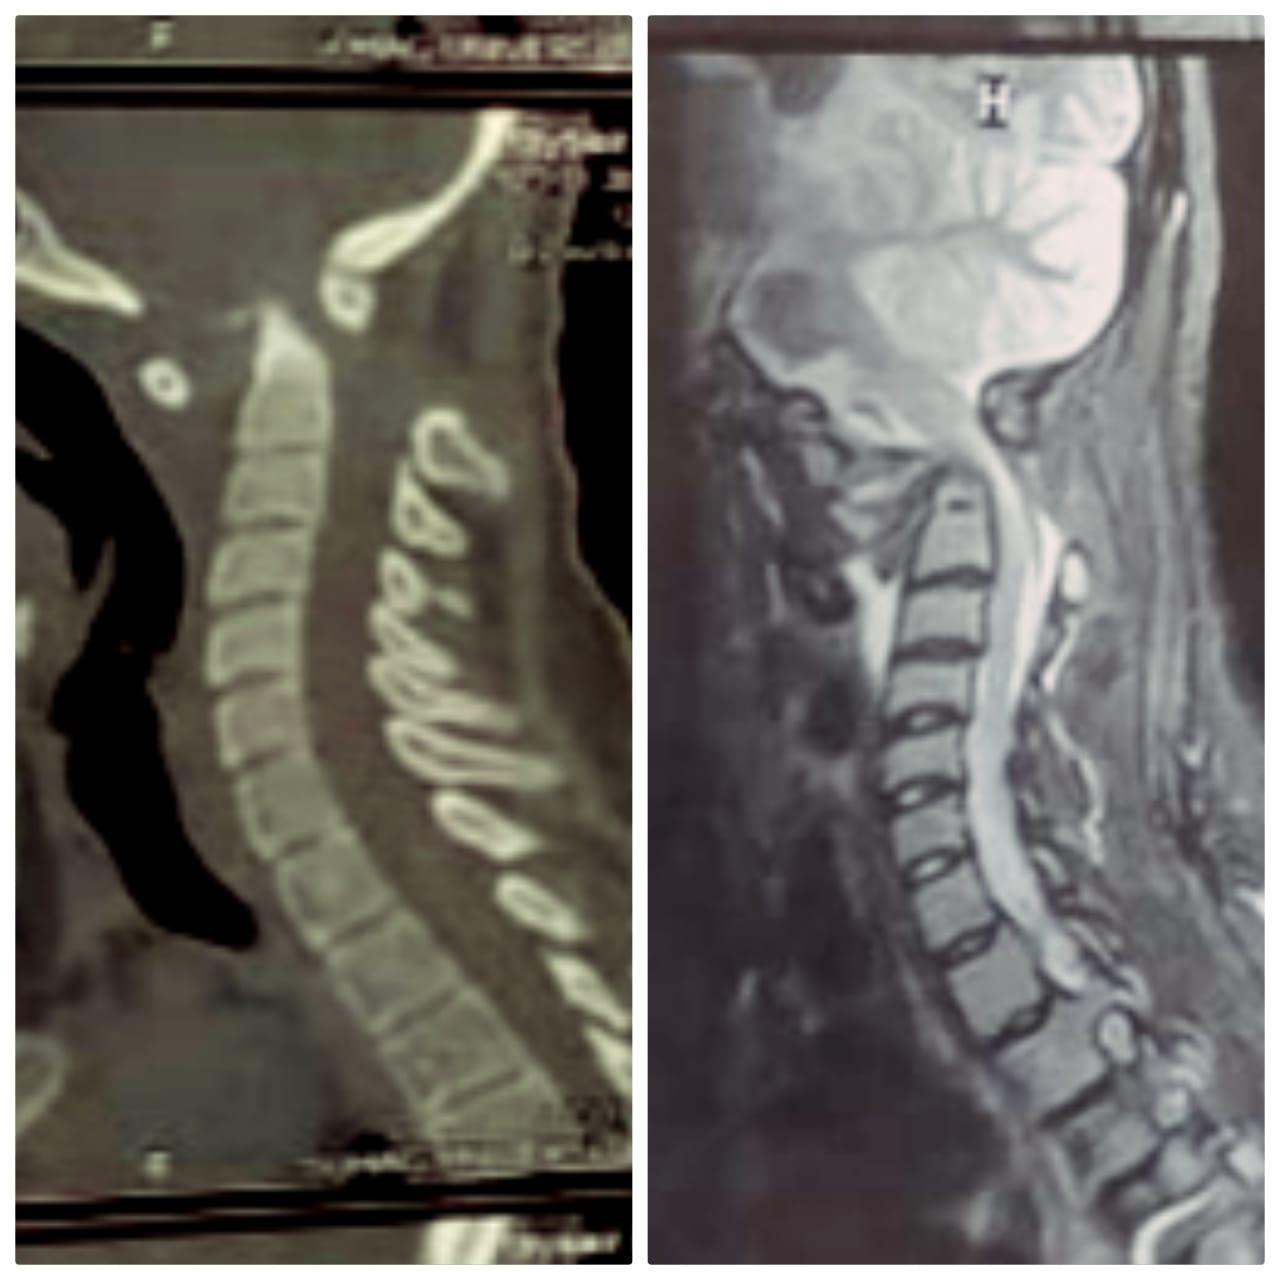

صرح الدكتور مصطفى عبدالخالق رئيس جامعة سوهاج، أن قسم جراحة المخ والأعصاب بالمستشفى الجامعي نجح في إجراء تدخل جراحي نادرًا ويعد الأول من نوعه في صعيد مصر، لفتاة تبلغ من العمر ١٨ عامًا، وتعاني من مرض خلقي الانغماس القاعدي مع عدم ثبات قاع الجمجمة في الاتصال بالفقرات العنقية، وهى من الحالات النادرة الحدوث، حيث أدى هذا المرض إلى إصابة الفتاة بشلل رباعي حاد نتيجة الضغط على الحبل الشوكى وجذع المخ بقاع الجمجمة.

وقال الدكتور مجدي أمين القاضي عميد كلية الطب البشري ورئيس مجلس إدارة المستشفيات الجامعية، إنه تم على الفور حجز المريضة بالقسم والتجهيز للتدخل الجراحي لتوسيع قاع الجمجمة مع استعدال الاعوجاج الفقرات العنقية وإعادتها إلى الوضع التشريحي الطبيعي وتثبيتها بقاع الجمجمة.